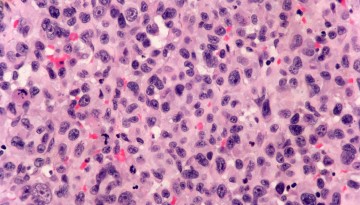

Researchers customize AI tools for digital pathology

Scientists from Weill Cornell Medicine and the Dana-Farber Cancer Institute have developed new AI tools tailored to digital pathology, a growing field that uses high-resolution digital images created from tissue samples to help diagnose disease.